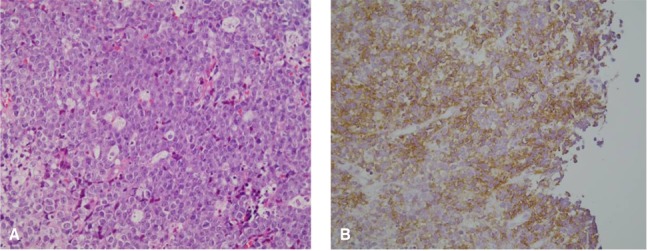

A 37-year-old male was admitted to our hospital because of his left sided hemiplegia that he had experienced for 3 months. He was known to be positive for HIV, as was determined during evaluation for idiopathic thrombocytopenic purpura in a foreign country about 6.5 years before this admission. At that time, he had been treated with zidovudine, lamivudine and saquinavir for the management of AIDS for 9 months and then he discontinued therapy of his own will. He was advised to restart treatment with zidovudine, lamivudine and indinavir at our hospital 4 years ago. He noticed weakness on the left side of his body during movement, which had slowly progressed and he finally developed left-sided hemiplegia 3 months previously. At the time of admission, he had complaints of headache and night sweats. He was diagnosed as having idiopathic thrombocytopenic purpura about 6.5 years ago and so splenectomy was done. Even after splenectomy, the thrombocytopenia continued. He was treated with steroid, vincristine, intravenous gammaglobulin, rituximab and danazole. He had also experienced liver abscess 4 years ago. He had received radiation for Kaposi sarcoma about 8 months before admission. On admission, the blood pressure was 90/60 mmHg, the pulse rate 100/min, the respiration rate 22/min and the body temperature was 38℃. Upon physical examination, the patient was in poor general condition with anemic conjunctiva. There were no signs of hemorrhagic diathesis or icterus. The laboratory finding were as follows; hemoglobin 7.4 g/dL, WBC 8,300/mm3 (neutrophila: 79.5%, lymphocytes: 14.6%, monocytes: 4.6%), platelets 10,000/mm3, erythrocyte sedimentation rate (ESR) 2 mm/h, AST 24 IU/L, ALT 9 IU/L, total bilirubin 0.7 mg/dL, LDH 473 IU/L, protein 3.9 g/dL, albumin 2.3 g/dL, BUN 9.5 mg/dL, creatinine 0.42 mg/dL, calcium 7.3 mg/dL, phosphorus 3.1 mg/dL, Na 130 mmol/L, K 3.0 mmol/L, the total number of CD4 and CD8 T lymphocytes was 46/mm3 and 621/mm3, respectively, and the ratio of CD4/CD8 was 0.07. The chest X-ray was not remarkable. Brain MRI (Figure 1A) shows 4 cm-sized round mass involving the right frontal lobe. The T1 weighted image and the T2 weighted image (Figure 1B) showed extensive areas of perilesional edema involving the right frontoparietal region and there was a mass effect upon the right lateral ventricle. Stereotactic biopsy of the brain lesion was performed, and histological examination disclosed atypical lymphoid cells with a predominant perivascular arrangement (Figure 2). Immunohistochemical examination showed positivity for CD20. The diagnosis of diffuse large B-cell lymphoma involving the CNS was made. The patient was treated with brain radiation. Sadly, he died of pneumonia 13 days after brain radiation therapy.

(A) The microscopic findings of the mass show a diffuse proliferation of large pleomorphic cells that contain abundant cytoplasm and large, round nuclei (H&E stain, ×400). (B) Immunohistochemical staining shows CD 20 positivity (×400).